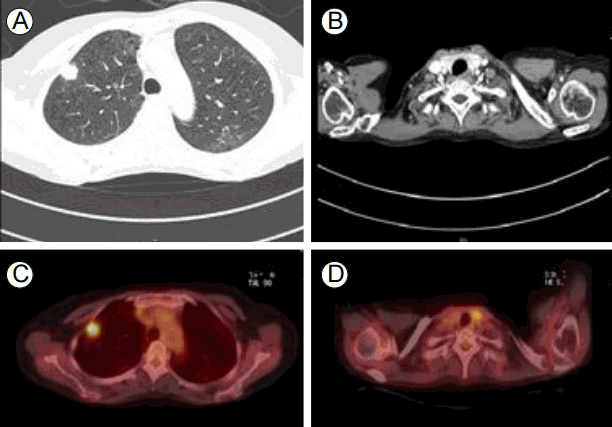

52세 여자 환자가 10년 전부터 서서히 진행되는, 차가운 곳에 있으면 생기는 손이 뻣뻣해지는 증상 및 피부건조 및 경화, 입술주위의 굳음을 주소로 본원 류마티스내과를 내원하여 전신성 경화증을 진단받았다. 진단 후 시행한 흉부 전산화단층촬영에서 폐의 종괴 및 갑상선 종괴가 발견되어 본원 종양내과로 의뢰되었다. 환자는 음주, 흡연력이 없었으며 특별한 감염의 과거력이 없었고 가족력상 특이 사항은 없었다.이학적 소견: 환자 입원 당시 만성 병색을 보였다. 입원시 혈압과 맥박은 각각 110/73 mmHg, 80회/분이었고 호흡수는 15회/분, 체온은 36.4ºC를 보였다. 신체 검진상 공막의 황달 및 결막의 이상 소견은 보이지 않았고 목에 만져지는 결절은 없었다. 가슴청진상 양쪽 폐하부로 작은 수포음이 들렸고 양쪽 손의 경한 저림과 통증을 호소하였는데 특히 왼쪽 손의 검지 부분에 상기 증상이 두드러졌고 피부의 경화 소견이 보였다. 양손의 색 변화는 관찰되지 않았고 압통이나 감각 저하가 보이지는 않았다(Fig. 1).검사 소견: 백혈구 6,100/mm3 (중성구 3,700, 60.3%), 혈색소 12.2 g/dL, 혈소판 228,000/mm3을 보였고 나머지 일반 생화학 검사에서 특이 소견은 보이지 않았다. 적혈구침강속도, C-반응단백 수치는 각각 16 mm/hr, < 0.5 mg/dL로 정상 범위였다. C4 20 mg/dL, C3 104 mg/dL, 항핵항체 양성(antinuclear antibody titration positive 1:310, speckled type), 항-SCL-70항체 양성, 항centromere항체 정상, 항-RNP항체 음성, 항DNA항체 음성을 보였다. 소변 검사상 특이 소견은 보이지 않았다. 갑상선 질환이 의심되어 시행한 갑상선 기능 검사상 thyroid stimulating hormone < 0.01 mIU/L, fT4 1.89 ng/dL, T3 93 ng/dL로 갑상선 기능 저하를 보였다.흉부 전산화단층촬영: 양쪽 폐에 전반적으로 젖빛유리음영이 보여 간질성 폐질환의 소견을 보였다. 우측폐의 상엽에 2.2 cm의 불규칙한 결절이 보이며 내부는 음영이 낮은 괴사된 부위를 포함한 폐암 소견이 보였다. 우상엽내 분절 및 아분절 기관지 주위로 병적으로 커진 림프절들이 있고, 이 병변들에 의해 우상엽 첨분절 기관지가 거의 막혀있는 상태였다. 늑막 벽의 침범 소견도 관찰되었다(Fig. 2A). 추가로 앞종격에 세포침윤 및 결절음영이 보여 흉선 증생(thymic hyperplasia)이 의심되는 소견이 보였다(Fig. 2B).복부 전산화단층촬영, 뇌 자기공명영상, 뼈 스캔: 암의 원격 전이 소견은 없고 특이 소견도 없었다.양전자 단층촬영: 우측 상부(Right superior)에 폐암으로 보이는 결절이 보였다(Fig. 2C). 갑상선 좌 옆에 두 개의 대사과다상태를 보이는 결절이 보였다(Fig. 2D).목 초음파: 좌 옆 갑상선의 낮은 극에 1.6 × 1.7 cm 크기의 암이 의심되는 결절이 보였고 양전자 단층촬영에서 대사과다상태를 보이는 부분과 일치하였다(Fig. 3).병리학적 소견: 우측폐의 우상엽에서 시행한 세포검사에서 분화도가 낮은 선암종이 보였고(Fig. 4A-4D) 상피세포 성장 인자 수용체 유전자(epidermal growth factor receptor gene) 검사에서 돌연변이가 검출되지 않았고, 역형성 림프종 키나아제(anaplastic lymphoma kinase) 유전자 검사에서 돌연변이가 관찰되지 않았다. 좌 옆 갑상선에서 시행한 세포검사에서 유두암종(papillary carcinoma)이 보였다(Fig. 4E-4F).치료 및 경과: 전신성 경화증을 진단받고 폐질환을 감별하기 위해서 시행한 흉부 방사선 소견상 우측 폐 상부의 2.2 cm 정도의 불규칙한 결절이 보였다. 폐암을 감별하기 위하여 흉부 전산화단층촬영을 시행하였고 폐암으로 의심되는 결절이 관찰됨과 동시에 갑상선의 크기 증가가 관찰되었다. 먼저 폐암을 진단하기 위해 폐결절의 생검을 시행하였고 병리학적 소견상 선암종(adenocarcinoma)이 관찰되었다. 폐암의 병기 설정을 위해 양전자 단층촬영을 하였고 늑막 벽의 암침윤 및 다수의 림프절 전이 소견을 보였고 비소세포폐암(non-small cell lung cancer), 선암종, T3N2M1, 병기 4기로 진단되었다. 양전자 단층촬영상 추가로 갑상선에서 결절이 보였다. 갑상선 결절에 대하여 추가로 초음파도 시행하였다. 갑상선 초음파상 갑상선 암으로 의심되는 소견이 보여 결절흡입술을 시행하였고 유두암종으로 진단되었다. 갑상선 유두암종이 관찰되었으나 비소세포폐암도 같이 진단받은 상태로 폐암의 예후가 더 안 좋음을 고려하여 우선 폐암에 대하여 premtrexed, cisplan으로 복합항암요법 2회를 시행하였고 반응평가상 부분관해(partial response)을 보였다. 추가적으로 2회(총 4회) 더 항암 치료하였고 반응평가를 위해 시행한 흉부 컴퓨터촬영에서 림프절의 크기 증가가 관찰되는 암의 진행(progression disease)을 보여 항암요법을 gemcitabine, cisplan으로 변경하였고 2차까지 진행 후 다시 암의 평가를 시행하였다. 반응평가상 암의 흉벽 침범 및 림프절의 크기 증가 등 암의 진행을 보였다. 이후 환자 전신상태 악화로 항암치료를 수행할 수 없어 보전적 치료 중이다.

Figure 2.

Computed tomography (CT) scan of the chest showing (A) a 2.2-cm primary lung cancer in the right superior lobe and (B) thymic hyperplasia. Axial positron emission tomography (PET) showing increased uptake in the right upper lung (C) and left thyroid lobes (D).